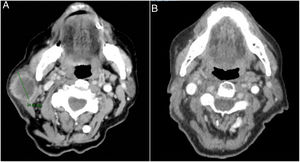

Se trata de una mujer de 83 años que se intervino de CEC moderadamente diferenciado e infiltrante de 8mm de espesor, sin invasión linfovascular ni perineural y márgenes respetados, en la rama mandibular derecha. La expresión del ligando de muerte celular programada (PD-L1) fue del 30% en células tumorales. Como antecedentes personales destacó el diagnóstico de un carcinoma ductal infiltrante de mama sin progresión y sin realizar tratamiento para ello. Tres meses tras la intervención desarrolló un conglomerado adenopático metastásico en el ángulo mandibular derecho de 4,5cm que se confirmó de carcinoma espinocelular, mediante punción aspiración con aguja fina. Se realizó radioterapia con intención curativa, con progresión de la enfermedad ganglionar y aparición de una masa de hasta 8cm cervical anterior. Ante la irresecabilidad de la enfermedad y su progresión a pesar de la radioterapia, con un ECOG de 0, se solicitó el uso de pembrolizumab off-label. Inició pembrolizumab a dosis de 2mg/kg cada 3 semanas, con una rápida disminución del tamaño tumoral tras 4 ciclos y presentando remisión completa clínica y radiológica de forma mantenida durante 6 meses (figs. 1 y 2). El tratamiento fue bien tolerado, presentando únicamente un síndrome similar a la polimialgia reumática, que cedió con analgésicos e hidroxicloroquina 200mg/12h. De forma paralela, el carcinoma ductal de mama no experimentó modificaciones en las mamografías de control.